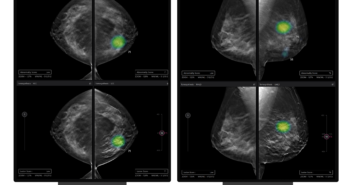

#의료인공지능기업 #루닛 이 미국 테네시주 녹스빌에 위치한 유방 전문 의료기관 #‘모자이크 브레스트 이미징’ 과 #유방암검진AI솔루션 #루닛인사이트DBT 및 #루닛인사이트MMG 등 2개 제품에 대한 공급 계약을 체결했다고 29일 밝혔다.